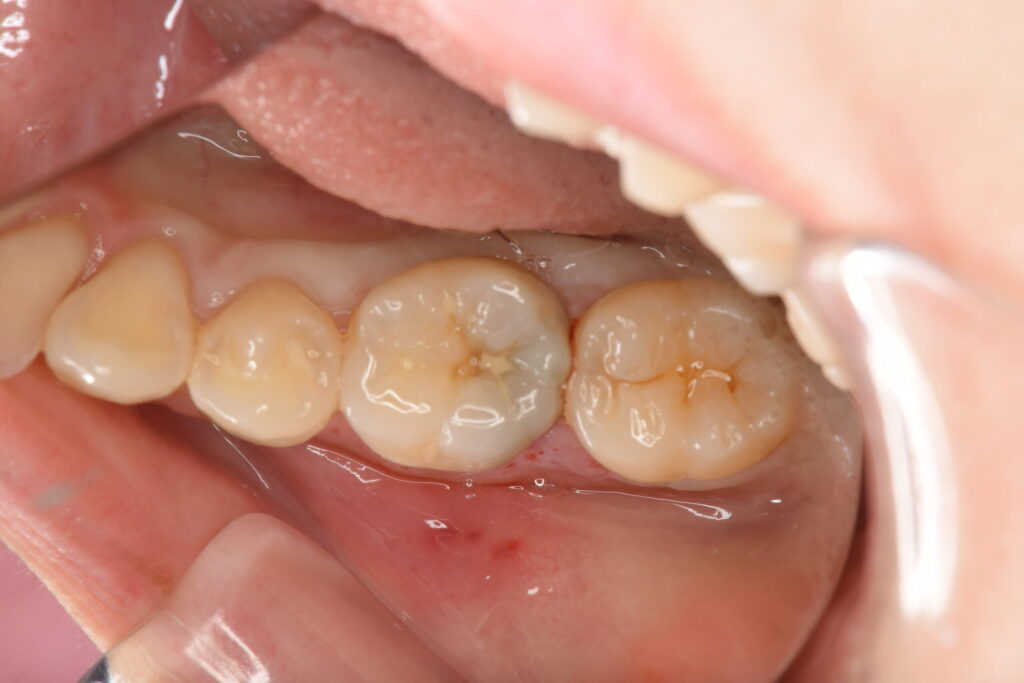

奥歯の痛みを主訴に来院されました。レントゲン検査にて神経近くまでの大きな虫歯が認められたため、MTAセメントによるVPT歯髄温存療法の選択肢とメリットデメリットを説明し、患者様はVPTを希望されました。

虫歯を除去する前に、ラバーダム防湿を行い清潔な状態を再現していきます。

消毒を行い、虫歯を時間をかけて丁寧に除去していきます。

青く染まっている部分が虫歯です

消毒を行い、神経に近い部分はMTAセメントを貼付します。

当日はレジンでの仮の蓋を行い、1ヶ月経過をみて痛みがないようでしたらオーバーレイでのセラミック治療を行なっていきます。(別記事にてその後の処置についてまとめてあります)